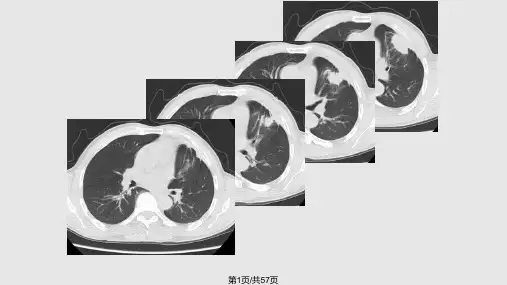

原发性肺癌

2.组织学分型:鳞癌,腺癌, 末分化细胞癌,细支气管肺泡癌,

3.放射学分型

(2)周围型:发生于段支气管及段以 下至细支气管以上

(2)周围型:实体性生长:癌细胞充满肺泡——沿 肺泡孔向周围生长——实性肿块

浸润性生长: 弥漫型:癌细胞——肺泡壁呈覆 壁生长, 肺泡充气,肺泡间隔无破坏 局灶性:病灶中心纤维结缔组织增生且 伴有炭末沉积——邻近支气管 牵拉向瘤体中心